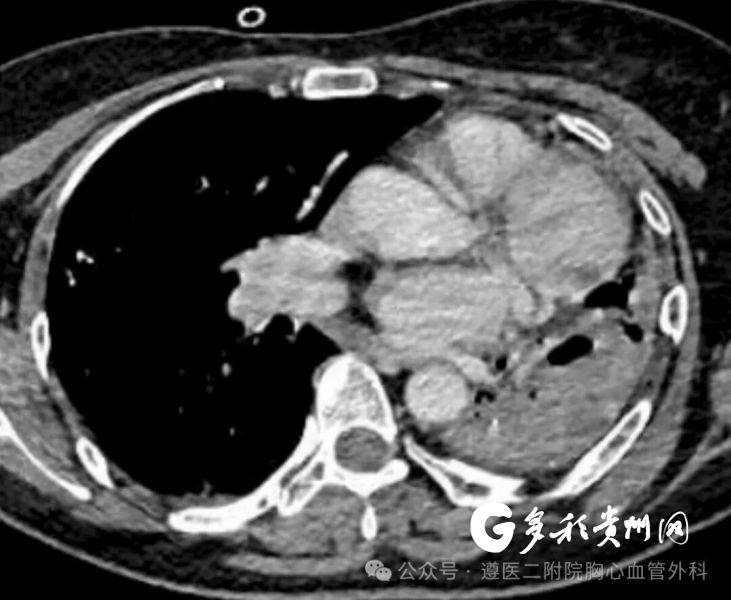

多彩贵州网讯 近日,遵义医科大学第二附属医院胸心血管外科成功救治了一名因“左侧结核性毁损肺”发生大咯血的危重患者。该患者自生病40年来反复发生咯血,本次发病咯血量大,检查提示左肺毁损已无功能,切除病肺止血救命刻不容缓。遵医二附院胸心血管外科团队在与死神的竞速中争分夺秒,顺利完成左侧胸膜腔粘连松解及全肺切除术,让患者转危为安,用精湛医术为患者筑起生命防线。

入院后,胸心血管外科团队迅速评估病情,结合患者病史与影像学检查,明确诊断为“左侧结核性毁损肺”。由于患者左肺已完全毁损且反复大咯血,保守及介入治疗均宣告失败,急诊手术成为唯一的救命选择。

但患者病程长达40年,左侧胸腔存在致密粘连,左肺上下叶组织已完全毁损,丧失功能,手术难度极大。术中可能面临大出血、气管、食管及主动脉损伤等凶险并发症,对团队技术与应急能力提出极大挑战。